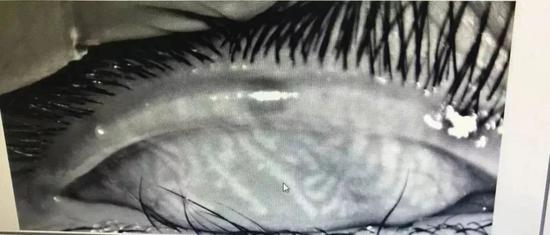

结果一做检查,主治医师洪楠看到小辛的睑板腺吓了一跳,“这哪是一个11岁小朋友的睑板腺,五六十岁的人情况都比这个好!”

正常人的眼睑上大约有32个睑板腺,平行竖线状排列,分泌油脂用来湿润眼球,而小辛的睑板腺已经“扭曲”成网状,模糊不清,相当于中老年人水平,甚至比有些中老年更差,所以眼睛会感觉到刺痛、灼烧感进而睁不开,并且小辛的睑板腺功能彻底恢复是不可能的,只能靠治疗来缓解症状了。

正常的睑板腺检查图

小辛的睑板腺检查图